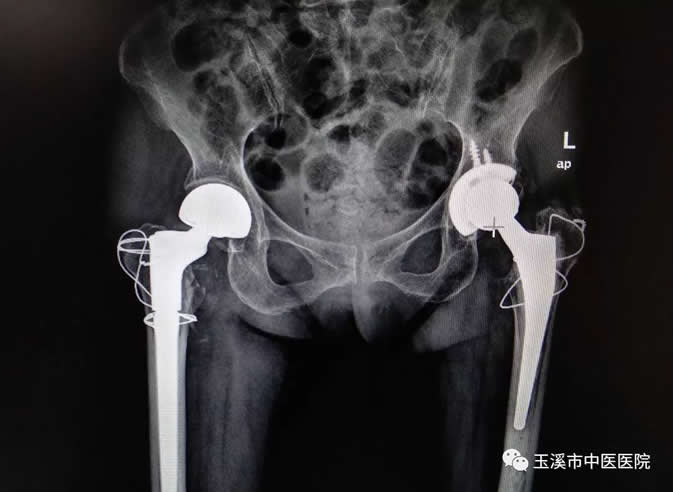

術(shù)后影像資料

近日,玉溪市中醫(yī)醫(yī)院收治了一位85歲的患者王奶奶,在4年前因跌倒致左股骨頸骨折到我院住院治療,行左側(cè)人工全髖關(guān)節(jié)置換術(shù)。2018年9月7日,王奶奶再次因為跌倒致右股骨粗隆間骨折至我院關(guān)節(jié)與運動醫(yī)學(xué)科(骨傷二科)住院治療,予患者行右側(cè)人工半髖關(guān)節(jié)置換,現(xiàn)患者已經(jīng)開始下地活動。對于老人家來說,經(jīng)歷了兩次“人生最后一次骨折”是“不幸”,但還能再次站立起來行走是“萬幸”。